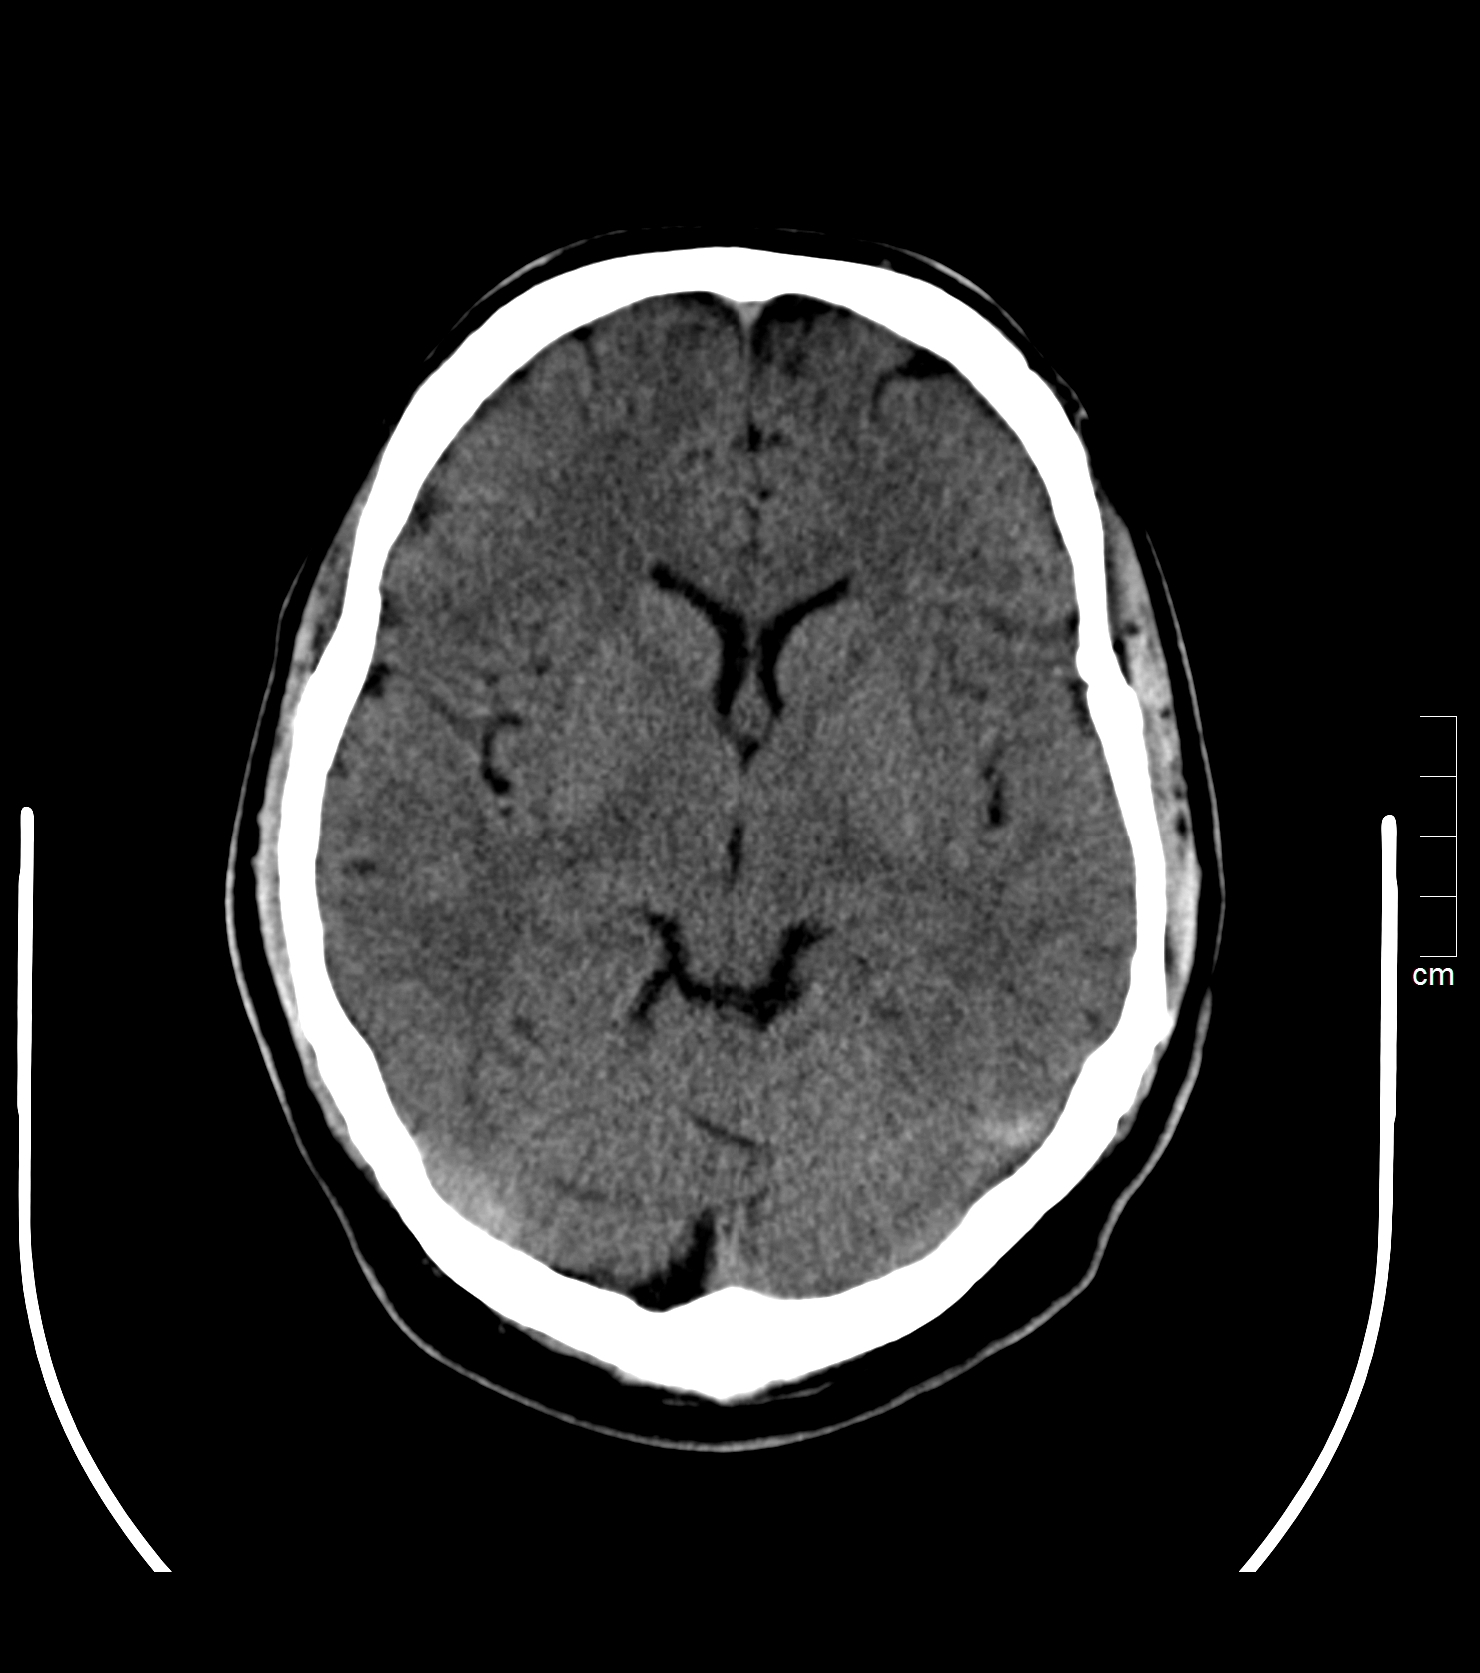

Bei der Computertomographie (CT) werden durch Röntgenstrahlung sehr dünne Schnittbilder des menschlichen Körpers erzeugt, welche die Beantwortung sehr vielfältiger diagnostischer Fragestellungen ermöglichen.

• Gehirn, Schädel, Innen- und Mittelohr, Nasennebenhöhlen